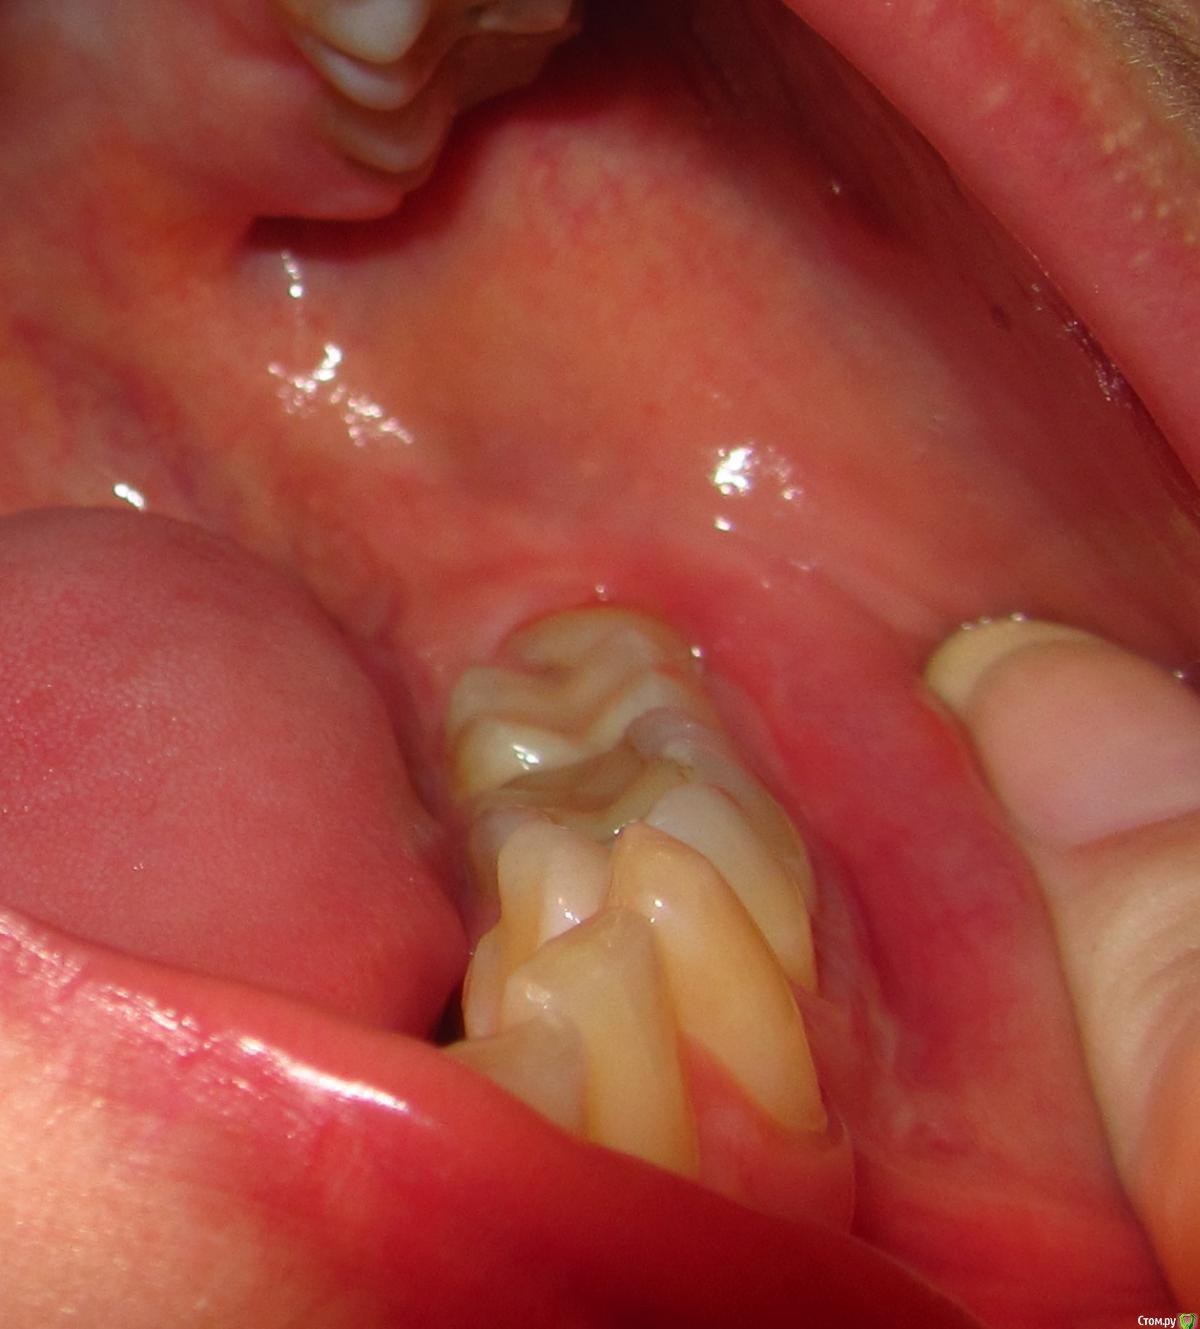

aqua1 Опубликовано 8 февраля, 2015 Поделиться Опубликовано 8 февраля, 2015 Добрый день! История моя давняя и до сих пор не решена….Где-то в 2007 году удалили в нижней 5-ке нерв, но зуб иногда «простреливал» при случайном накусывании по ночам. Подозреваю, что неудачное лечение могло быть связано с тем, что немного передержали лекарство, так как врач был в отпуске..Через полгода, в 2008 году на десне между 5 и 6 образовался бугорок, снимок показал воспаление на корне. Так как каналы на снимке были запломбированы хорошо, сказали что нет смысла их перелечивать, и зуб придётся удалить(( Естественно, меня такой поворот не устраивал, зуб был хорошо сохранен, никогда не беспокоил, и лечение кариеса изначально было просто профилактическим, но канал оказался слишком близко... Второй вариант был антибиотики, образовался свищ, а вскоре всё зажило и припухлость полностью спала (хотя на снимке 2009 года ситуация не изменилась).Ни зуб, ни дёсны не беспокоили меня абсолютно до весны 2012 года, когда после ветреной погоды, зуб поныл 2 дня и образовалась даже не припухлость, а затвердевшая дуга вдоль 6-8 зубов. Боли и воспаления не было. Испугавшись, что это будет расти и дальше такими же темпами, поехала в стоматологию, где терапевт отправила меня к хирургу, у которого было 2 варианта – резать или вырывать. На новом снимке никаких изменений опять замечено не было.. Десну разрезали между 5 и 6, гноя не было, потом отёк сошёл, а затвердение нет.В настоящий момент оно особо не беспокоит, только иногда ощущается в челюсти, асимметрии лица тоже вроде не заметно. В 2014 году начала активно лезть полулежачая восьмерка, без боли и воспаления. Затвердевшая дуга на десне начинается под 6-м зубом и плавно уходит за эту 8-ку. По случаю всего этого в январе 2015 сделали панорамный снимок всей этой красоты.Очень нужны ваши советы!1) Обязательно ли удалять эту 5-ку или как её лечить? Сойдет ли затвердение на десне после удаления? Что это вообще может быть?2) Я так понимаю, что 8-ка на удаление. Стоит ли немного подождать, пока она вылезет побольше, чтобы легче её удалить?Заранее спасибо. Прилагаю всю историю в рентгенах, а также фото, как это выглядит сейчас вживую. Ссылка на комментарий

aqua1 Опубликовано 8 февраля, 2015 Автор Поделиться Опубликовано 8 февраля, 2015 (изменено) Разъяснения по снимкам:1) весна 2008 года - начало2) 2009 год3) весна 2012 года - сразу после обострения и появления отвердевшей десны4) свежий снимок 2015 года5) так выглядит зуб мудрости4) зубы и десна в обычном состоянии7) и 8) - изображения отвердевшей дуги на десне вдоль 6, 7 и 8 зубов (т.е. та область, что между зубами и пальцем) Изменено 8 февраля, 2015 пользователем aqua1 Ссылка на комментарий